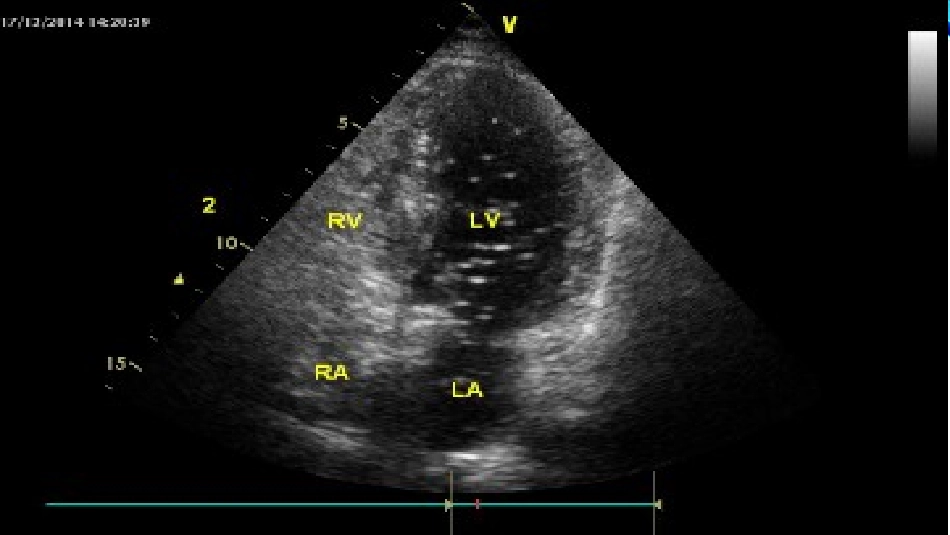

右心声学造影葛士骝定义•什么是右心声学造影:•右心声学造影是经外周静脉注入造影剂,造影剂气泡直径>10微米,平均约15微米,不能通过肺毛细血管网,不进入左心系统。由于微泡与血液存在明显声阻抗差,即使个别微泡(低速微量血流)也能清晰显示,根据显影顺序、途径和时间对某些结构和血流异常做出诊断和鉴别诊断。造影剂种类•1,双氧水造影剂:•3%双氧水,按0.01ml/kg计算;•2,二氧化碳造影剂:•5%碳酸氢钠10ml+5%维生素C(PH值2.0)5ml;•5%碳酸氢钠5ml+5%醋酸1ml;•5%碳酸氢钠4ml+1%稀盐酸1ml;•5%碳酸氢钠5ml+维生素B6300mg。•3,手或声振微气泡造影剂:•生理盐水10ml+空气约0.3ml手动制备;•50%葡萄糖或76%泛影葡胺或5%白蛋白6~8ml注射及检查方式•注射方法:•建立左或右肘静脉通道(永存左上腔只用左侧),与上述三通开关相连,当造影剂制备完成后,迅即转换三通开关推注造影剂。•检查方法•首先行常规超声心动图检查,了解心脏结构,明确心内有无缺损及大小,观察心内分流水平及分流类型。再经左肘静脉快速推注生理盐水微泡造影剂,观察心腔内房室显影顺序、心腔大小、室壁厚度、有无占位病变,右向左分流的有无及多少、光点密度、起始时间及滞留时间等。为提高右向左分流的检出率,嘱患者进行Valsalva动作或用力咳嗽,增加右心房压力,使血流发生右向左分流。适应症•卵圆孔未闭(PFO):发生率约20%,多无临床意义,少数存在右向左分流•可能与以下病变有关:矛盾性栓塞-(不明原因脑缺血事件);气栓-减压病(潜水时发生);脂栓-手术后神经系统功能失常;低血氧-斜卧呼吸直立性低血氧(见于老年人);顽固性低氧血症-RV梗死、PE、TV等病变时……;偏头痛-有视觉异常等先兆症状,反复发作•PFO超声诊断•2DE直接征象(确诊):原发隔与继发隔交界重叠处存在明确缝隙;彩色多普勒见过卵圆孔斜行细小分流(不论方向)(TEE检出的敏感性和特异性明显高于TTE);2DE间接征象(疑诊):存在房间隔膨出瘤;卵圆窝较薄存在明显摆动幅度。•右向左分流的诊断(具有临床意义):彩色多普勒见双向或右向左分流;•右心声学造影:右房显影后有“暂短”气泡进入左房(后者对右向左分流检出的敏感性和特异性明显高于CDFI)•右心造影与PFO临床关系PFO分流量••少量——微气泡<10个/每帧•中量——微气泡10-30个/每帧•大量——微气泡>30个/每帧•高危PFOl•TEE测定PFO为4±2mml静息状态下存在R-L分流存在房间隔膨出瘤右心造影,造影剂充填左房50%l右心声学造影,左房内微泡>50个/每帧•肺动静脉瘘(PA-VF):属罕见先心病。临床部分有紫绀,背部可闻及低调连续性血管杂音。2DE房间隔完好,其他心脏形态结构无特征性改变,CDFI无心内异常血流。•右心声学造影:根据瘘口位置和大小不尽相同。•迟发左心显影(右心显影后4~10个心动周期);•造影剂来自左/右肺静脉,呈连续均匀;•右心显影消退或消失时,左心显影仍明显或存在。•冠状静脉窦扩张(CVSD):CVSD有多种原因,其中永存左上腔(PLSVC)最常见(约90%),单发PLSVC无临床意义。但需与肺静脉异位引流…等其他可能导致CVSD的病变鉴别。体外循环手术者合并CVSD时需排除PLSVC,以免发生体外循环意外。但PLSVC的直接显示往往困难。•右心声学造影:左上肢静脉推注造影剂后,冠状静脉窦、右房、右室顺序显影。•PDA合并重度肺高压:典型PDA表现:PV区粗糙连续性杂音。2DE显示左心扩大,肺动脉增宽。CDFI见特征性PDA开口处双期左向右分流。但当重度肺高压时,原有杂音和分流都减轻甚至消失,右心增大为主,左、右心内径比例逆转,易误诊和漏诊。•右心声学造影:当右心、肺动脉顺序显影后,可见造影剂经PDA进入降主动脉-腹主动脉。•房间隔缺损合并肺动脉压力增高:定性诊断不是问题,但部分患者肺动脉、右心压力增高,两侧心房压力接近,分流速度低,CDFI对是否存在右向左分流判断模糊。可借助右心声学造影。•右心声学造影:上肢静脉推注右心声学造影剂,右房显影后通过观测是否有造影剂进入左心房以及进入的微泡数量很容易对房缺的分流状态作出评估。•VSD左向右分流:常见膜周部室间隔缺损诊断较容易,...